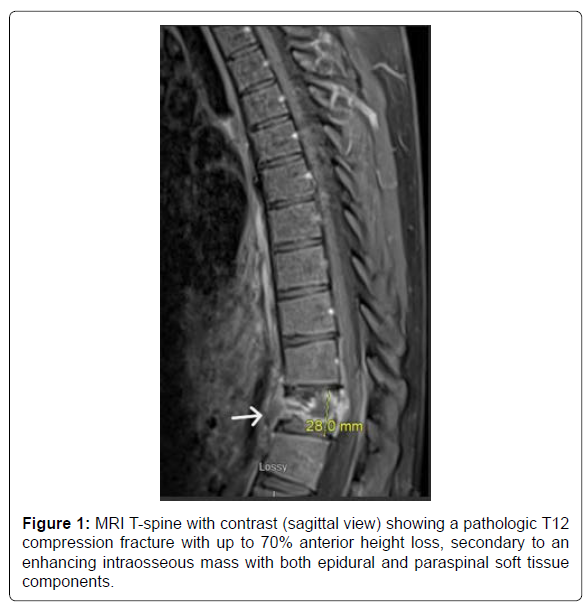

A 20-year-old male with no known significant past medical history presented with a 2-month history of lower back pain that acutely worsened on the day of presentation. Physical examination was positive for lower thoracic and upper lumbar spinal and paraspinal tenderness and negative for any focal neurological signs. Initial labs were only positive for mild leucocytosis (Table 1). MRI T-spine with contrast revealed a solitary intraosseous lytic mass at T12 with both epidural and paraspinal components and a pathological compression fracture (Figure 1). Pediatric Oncology and Neurosurgery were consulted, based on the tumor characteristics, Langerhans’ cell histiocytosis and Ewing sarcoma were sought higher on the differential. The patient was started on high-dose steroids, dexamethasone 20 mg IV every 6 hours. An IR soft tissue biopsy was performed, which showed giant cell proliferation concerning for GCTB (Figure 2). On day 12, the patient underwent corpectomy with tumor resection and surgical stabilization via posterior T9-L3 spinal fusion and placement of an Ulrich expandable cage graft. The biopsy confirmed the diagnosis of osseous giant cell tumor (Figure 3).

The patient did not follow up with any of the specialties after the discharge owing to poor socioeconomic support. He presented back to the hospital exactly three months after the discharge with symptoms of left and right-sided flank pain, worsening lower back pain, and fatigue. He was noted to have the dehiscence of the lower surgical incision site on examination. The patient was admitted for evaluation and management of a non-healing surgical wound. The patient was empirically started on IV ceftriaxone and Vancomycin for soft tissue infection. CT T and L-spine with contrast demonstrated recurrence of the soft tissue mass in the post-corpectomy space, extending into the central canal and measuring 8.3 x 6.5 cm, bilateral paraspinal fluid collections, and probable destructive lesions or bone erosions in the inferior endplate of T10-11 and the superior endplate of L1 (Figure 4). MRI T-spine with contrast had motion artifact related to cage graft, but within the limitations, showed similar findings of tumor recurrence (Figur 5). CT chest with contrast demonstrated extensive new soft tissue lung nodules, the largest nodule of 6mm, compared to CT from the previous admission, consistent with extensive lung metastases. The nodules were deemed too small for biopsy by the IR and the pulmonologist.